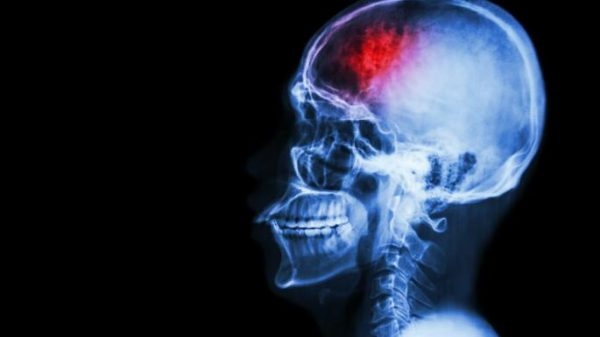

Chấn thương sọ não là tình trạng hộp sọ và các cấu tạo bên trong hộp sọ bị tổn thương khi bị sang chấn vào đầu.

Chấn thương sọ não thể nặng là những chấn thương ở mức độ nặng, chẳng hạn tăng áp lực nội sọ, chảy máu não, thiếu máu não, phù não…Những chấn thương này nếu không được phát hiện và điều trị kịp thời sẽ dẫn đến hậu quả cực kì nguy hiểm, khiến các dây thần kinh hộp sọ bị tê liệt, bị động kinh, rồi loạn tâm thần làm cho người bệnh khó vận động, thậm chí tê liệt toàn thân.